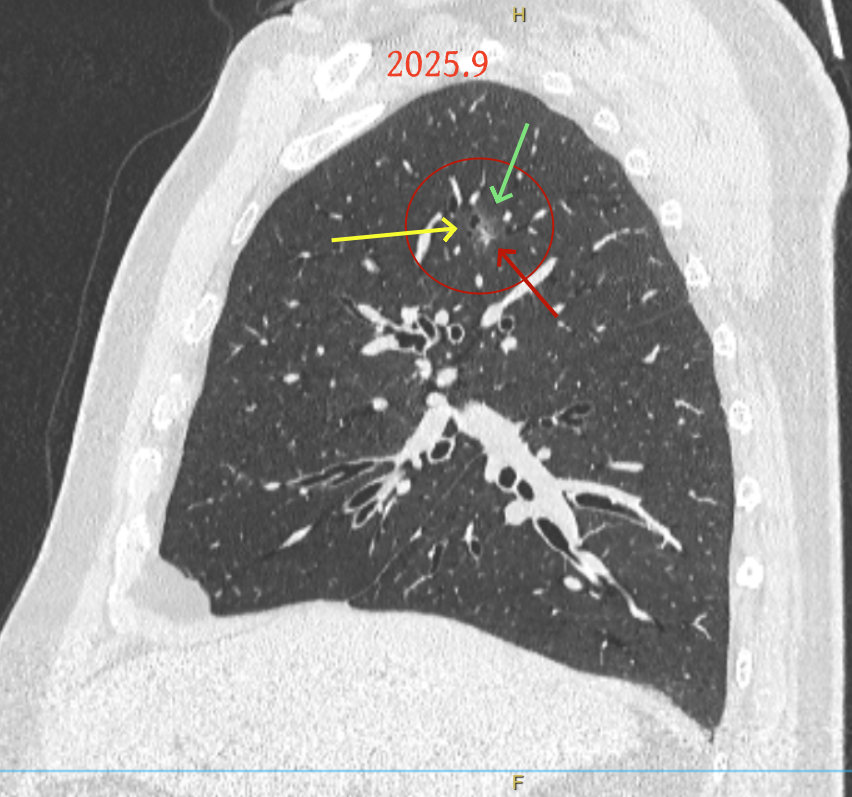

方形的是25年的,红色的主病灶,磨玻璃密度伴少许略偏高点密度,但还说不上典型混合磨玻璃病灶,考虑原位癌或微浸润性腺癌可能性大;蓝色的轮廓与边界欠清,位置靠上叶中央,无法段切或楔切;黄色的多发均淡而纯,分布在两肺。圆形粉色的是主要的两处23年时的样子,对比说不上很明显进展。鉴于若手术得切肺叶,何况两肺他处仍的结节,年纪又74了。我倾向保守点,先6-9个月复查,等进展并风险增加再来考虑怎么办的事。意见供参考!

病灶B似乎灶内有少许密度略偏高,但瘤肺边界欠清晰,总体说不上太显著的进展。

当时结友自己还觉得有点实性成分,血管感觉也有增粗。而我觉得整体密度仍是磨玻璃,轻微的变化仍不足以影响临床决策的程度。

病灶没有确切纵隔窗可见的实性成分,但与血管关系较为密切。

病灶A以及他处磨玻璃结节其实进展都是不明显的,略与2022年比,病灶A稍显明显点。病灶B开始时极淡,之前进展虽有但也甚微,直到2025年9月仍是磨玻璃成分为主,只是点状少许密度稍高成分。但在最近半年内却显然进展!若从影像上判断,基本上就得是浸润性腺癌了。那有几点:一是必不能再随访;二是大小来看仍是1A期;三是从快速进展来说,可能含有部分高危亚型,比如微乳头或实体型等;四是他处的磨玻璃结节以及病灶A显然不能用病灶B的转移来解释,仍考虑是多原发早期肺癌。

这是较为少见的一个病例,磨玻璃为主,而且一直瘤肺边界欠清晰的病灶何以会在之前三年均极缓慢微小变化的情况下,近半年却快速进展呢?从影像细节上看,我们能否进一步分析哪种纯磨玻璃结节可能会较快进展?结合本例,我个人的考虑是:1、病灶整体显得是磨玻璃密度,但灶内并不均匀,就如磨玻璃密度中混入细沙状;2、整体轮廓虽然较清但瘤肺边界相对来说却并不太清晰;3、邻近有血管紧挨,而且与病灶这间缺乏间隙;4、病灶密度不高,没有明显实性成分,却有灶内有细支气管通气征,说明肿瘤成分具有收缩力,却与纯磨的收缩不匹配(纯磨一般不太会有明显收缩力)。如果有上面这些特征可能要提高警惕,一是适当较短的随访间隔,二是影像细节变化要更加注意,开始变化意味着已经进入发展期,而非蛰伏期。当然是否在2025年9月时定得手术了?如果是孤立性的病灶B,且位置位于能简单楔形切除的位置,那是可以考虑的。但位置深、两肺多发,切除范围不小,再今年据肺癌诊疗指南中说的混合磨玻璃结节实性成分不足25%是非侵袭性病变,且几乎不会转移,那么按原则仍再随访显然是可以的。本例的随访变化再次表明磨玻璃密度肺癌的诊疗个体化之路仍是很漫长的,按指南原则的随访或诊疗显然不足以覆盖所有病例,总结与经验积累永远在路上。